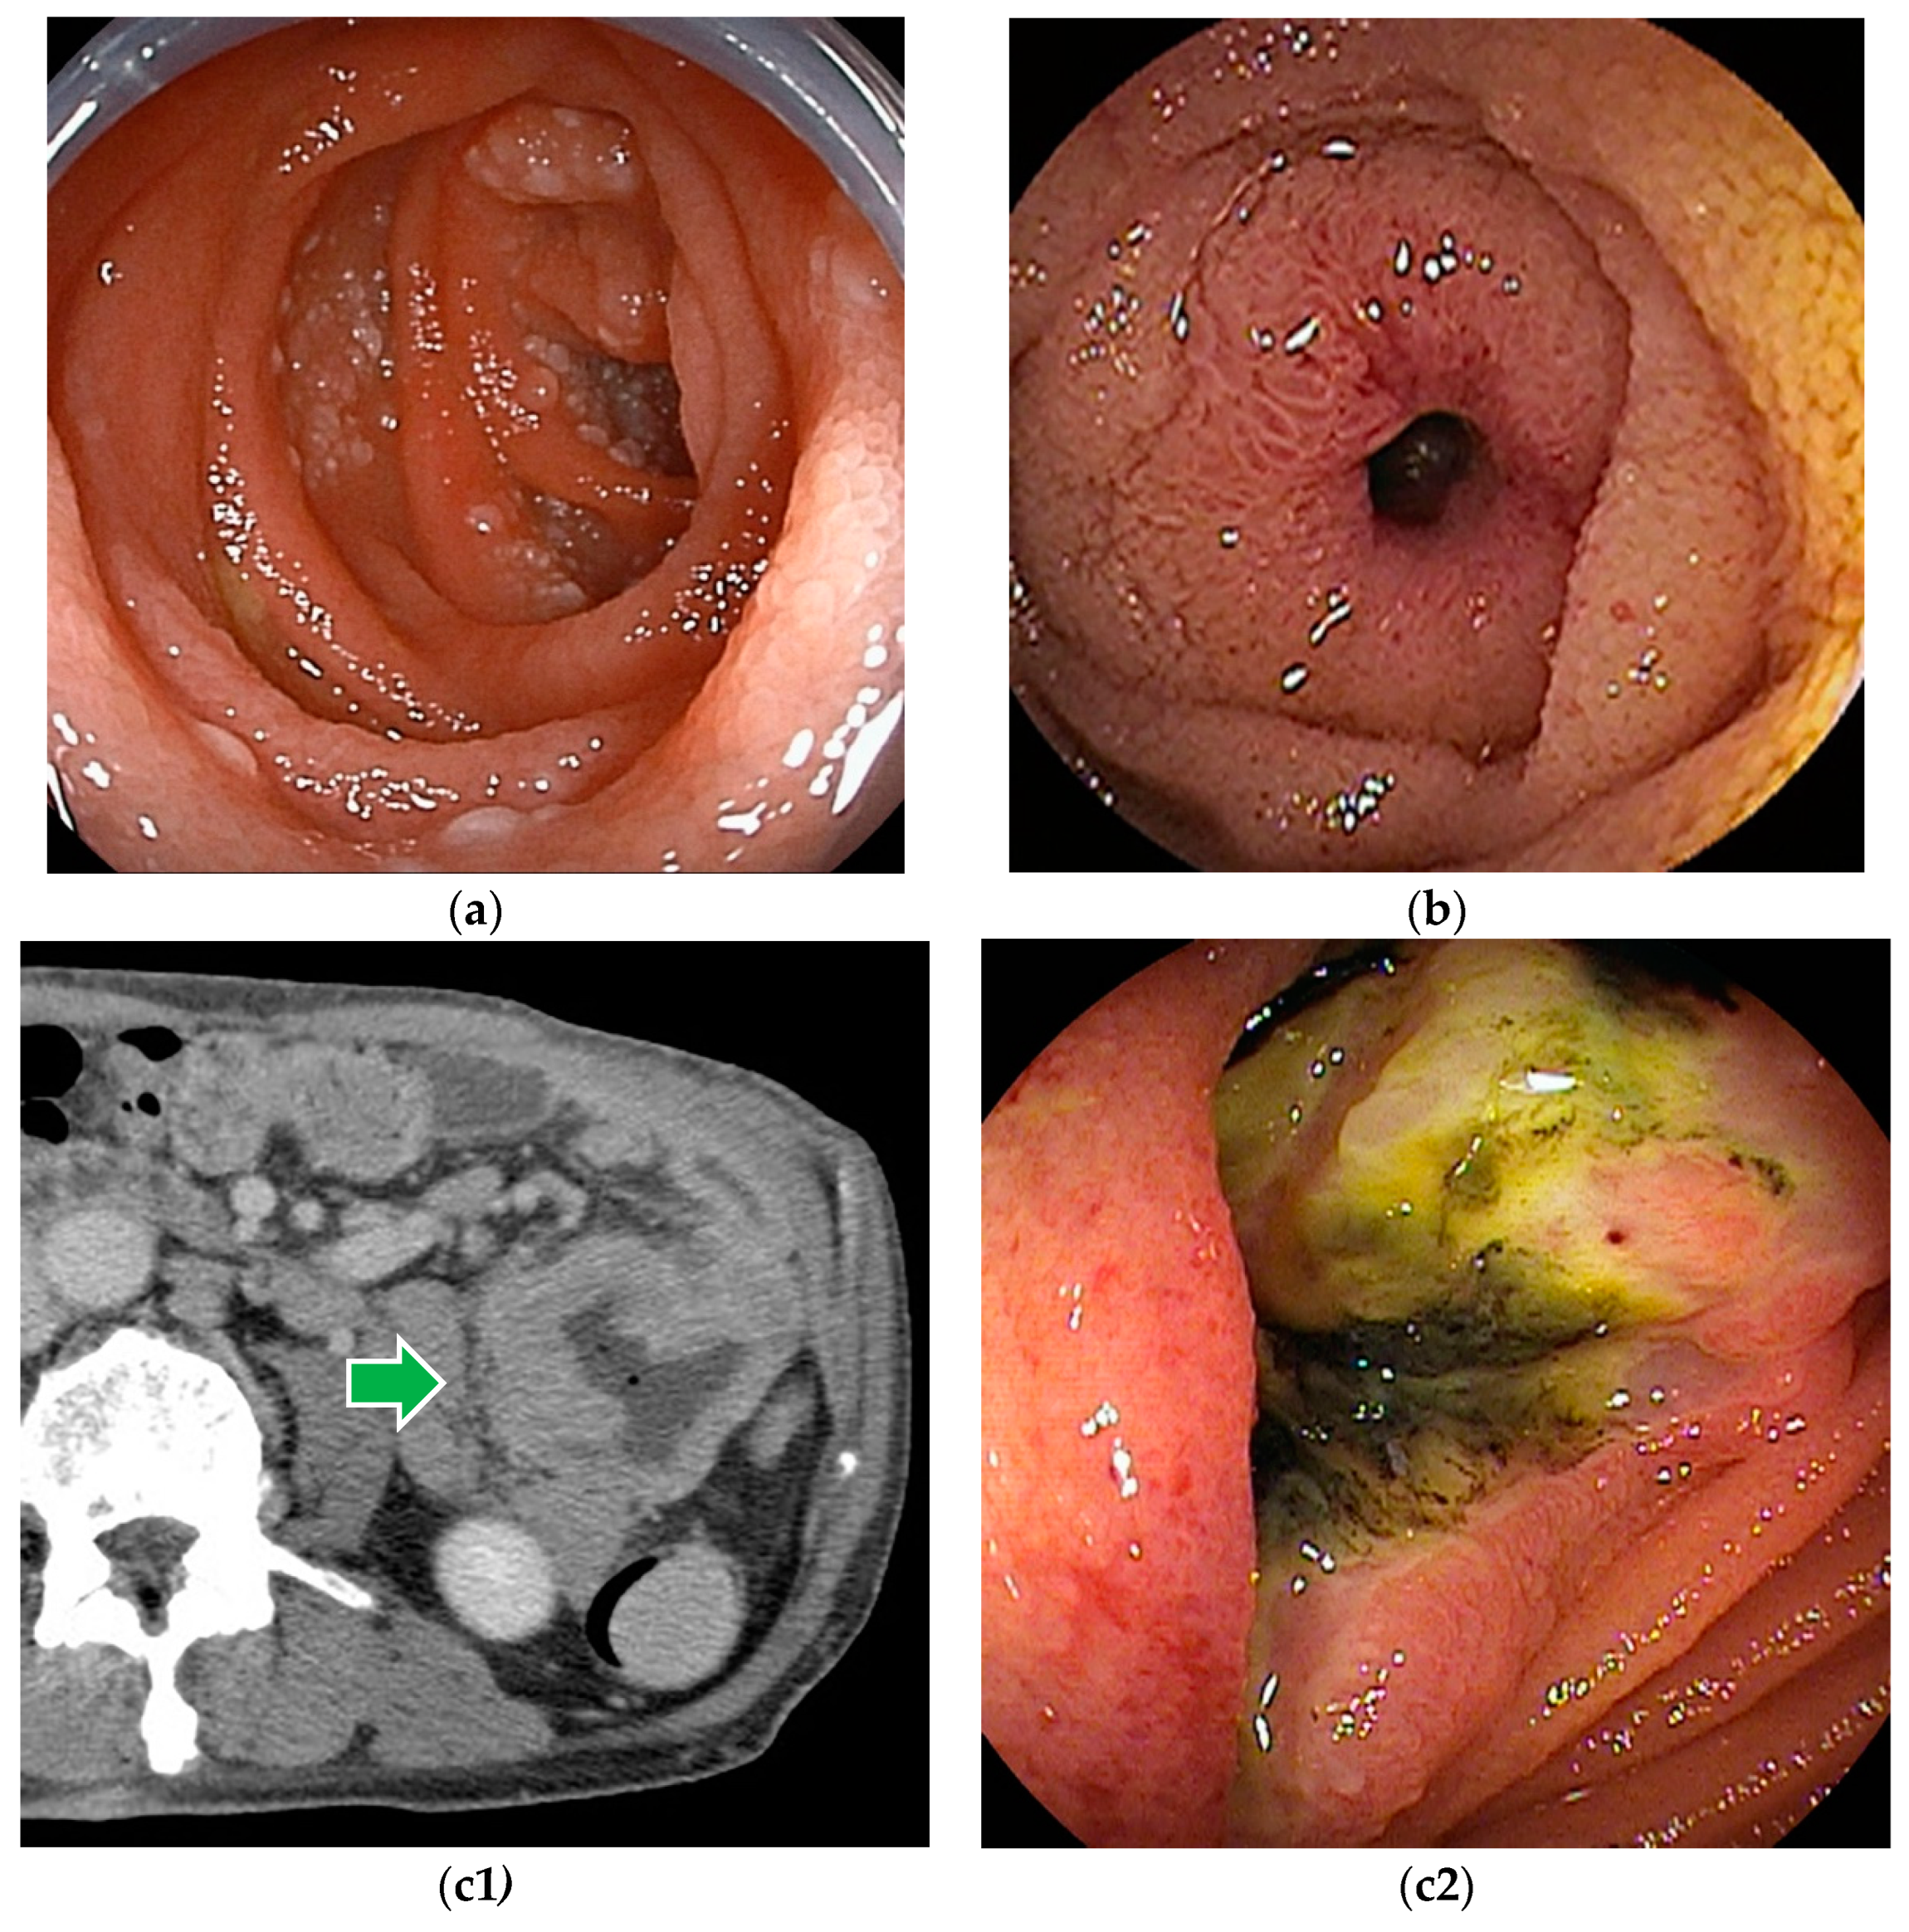

Figure 3.

Malignant lymphoma: (a) Follicular lymphoma is characterized by aggregations of large and small white granules. The lesions are distributed focally from the duodenum to the jejunum. (b) Rarely, it may be a form of concentric stenosis with ulceration. (c1,c2) Diffuse large B-cell lymphoma (DLBCL) often shows an ulcerated or polypoid morphology, and the biopsy should be taken from the ulcer bed rather than from the edges. CT revealed a wall-thickened intestine with a dilated lumen. DBE showed an ulcerated lesion.

Although endoscopic findings of malignant lymphomas vary by histologic type (Figure 3), a definitive histopathologic diagnosis can be made by biopsy in most cases. Based on the histopathologic diagnosis, lymphomas can be treated with chemotherapy [26,27]. However, in cases of bleeding or obstructive symptoms, chemotherapy is given after surgical treatment.